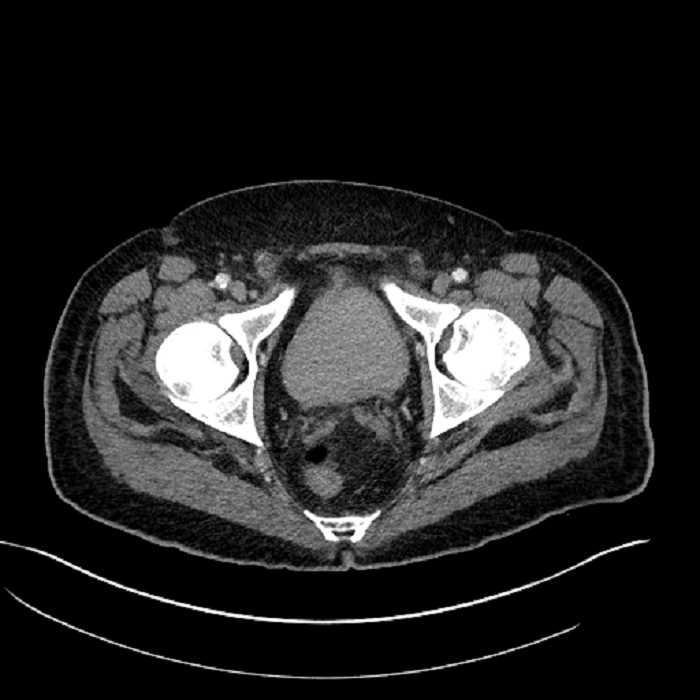

Age: 63

Sex: Male

Indication: Abdominal pain

• Mild mural thickening of a segment of the sigmoid colon with adjacent fat stranding and a 1.5 cm fluid and gas collection along the tip of an inflamed diverticulum

• Loss of the normal fat plane between this collection and adjacent loops of small bowel, which demonstrate mural thickening

• High grade stenosis of the left common iliac artery, with the left internal and external iliac arteries remaining patent

• Ankylosis of both sacroiliac joints

Acute sigmoid diverticulitis complicated by a small contained perforation and a large abscess in the right hepatic lobe. Additional small subcapsular abscesses along the anterior margin of the left hepatic lobe.

Additionally, loss of the normal fat plane between the peridiverticular collection and adjacent thickened loops of small bowel raises the potential for an enterocolonic fistula.

High grade stenosis of the left common iliac artery. The left external and internal iliac arteries are patent.

Hepatic abscess showing the double target sign with low density internally surrounded by a thin inner enhancing rim (red arrow) and ill-defined outer low density rim (yellow arrow). Blue arrow indicates an internal septation. Red arrows: additional smaller subcapsular abscesses. Red arrow: focal contained perforation associated with diverticulitis.